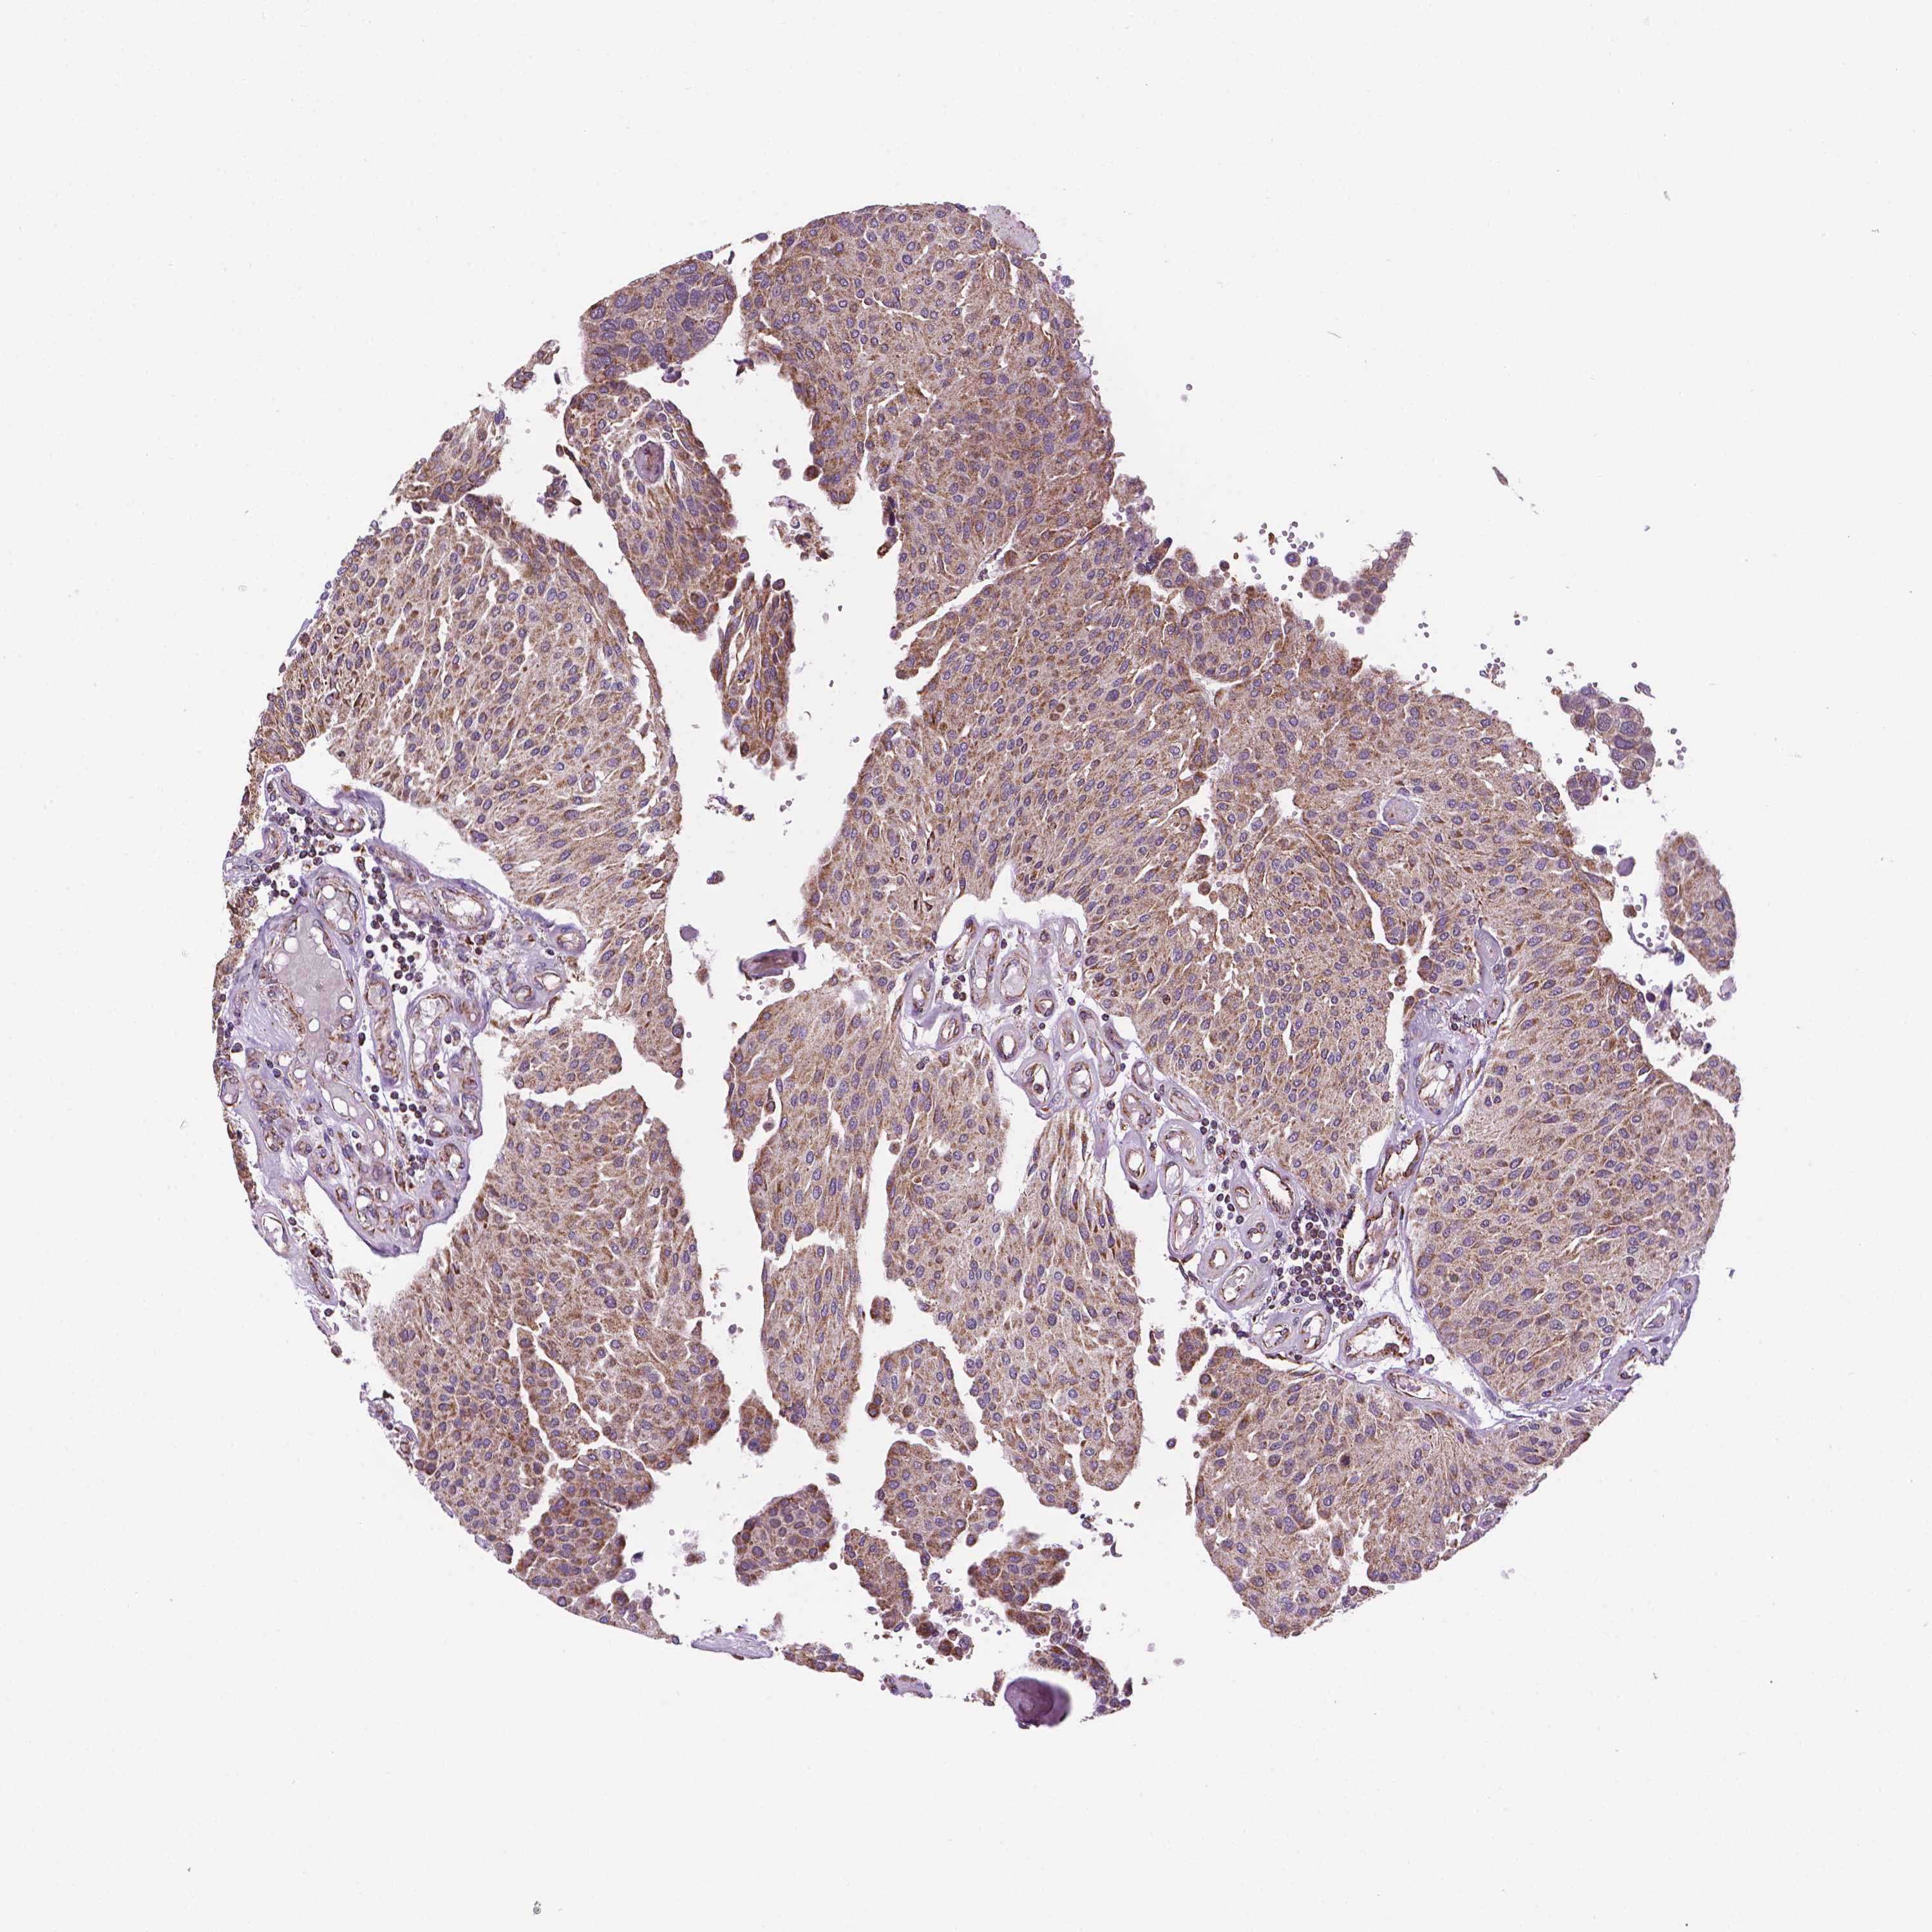

UROTHELIAL CANCER - Protein expressioni

A mouse-over function shows sample information and annotation data. Click on an image to view it in a full screen mode. Samples can be filtered based on level of antibody staining by selecting one or several of the following categories: high, medium, low and not detected. The assay and annotation is described here.

Note that samples used for immunohistochemistry by the Human Protein Atlas do not correspond to samples in the TCGA dataset.

Antibody stainingi

Antibody staining in the annotated cell types in the current human tissue is reported as not detected, low, medium, or high, based on conventional immunohistochemistry profiling in selected tissues. This score is based on the combination of the staining intensity and fraction of stained cells.

Each image is clickable and will lead to virtual microscopy that enables deeper exploration of all samples and also displays staining intensity scores, fraction scores and subcellular localization as well as patient and tissue information for each sample.

Antibody HPA067891

Staining

High

Medium

Low

Not detected

Intensity

Strong

Moderate

Weak

Negative

Quantity

>75%

75%-25%

<25%

None

Location

Nuclear

Cytoplasmic/membranous

Cytoplasmic/membranous,nuclear

Urothelial carcinoma, High grade

Urothelial carcinoma, NOS

Urothelial carcinoma, Low grade